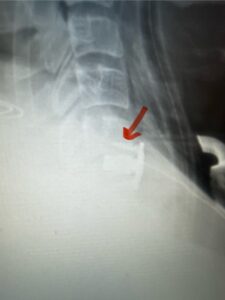

Fig. 4: Intraoperative lateral cervical x-ray demonstrating anterior cervical construct in good position at C 5 6 (red arrow)

A 37-year-old male police officer complained of a one-month history of difficulty with his balance and leg weakness. He complained of achiness in his legs. He also complained of bilateral arm weakness and numbness of his hands. He was also having difficulty writing due to the weakness. Patient had an MRI of the cervical spine which demonstrated a disc/osteophyte at C56 causing spinal cord compression and concurrent myelomalacia (Fig. 3). Patient underwent an anterior cervical discectomy with a cage and plate (Fig. 4). He tolerated the procedure well with improved numbness and weakness. This is a young person with fairly extensive myelomalacia and a fairly rapid development of symptoms. For this it was felt surgery was indicated. How he will do will depend on how much of his symptoms was caused by the compressive component or intrinsic damage to the spinal cord. As a rule, patients generally improve to some extent quickly; but their recovery of their spinal cord function can sometimes take up to 2 years to realize the extent of their improvement. Patients have to be patient with themselves in terms of their expected recovery.